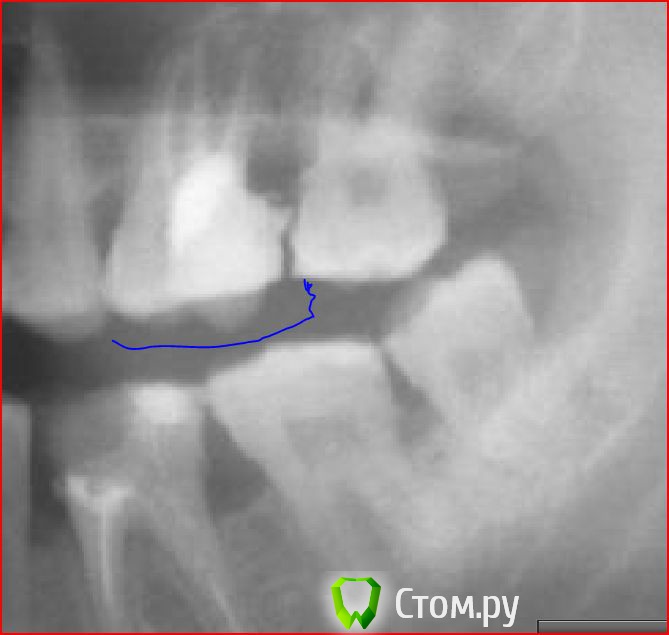

selis Опубликовано 28 ноября, 2014 Поделиться Опубликовано 28 ноября, 2014 На панорамой съемке (прилагаю Как мне сказали необходимо переделать пломбу поскольку она способствует созданию десневого карманаВопрос - не приведет ли снятие рассверлвание зуба к его ослаблению хрупкости ? может сразу уже штифт ставить? Ссылка на комментарий

Shaid Опубликовано 28 ноября, 2014 Поделиться Опубликовано 28 ноября, 2014 Карман, действительно, есть(даже костный, не десневой). Возможно, там уже нужна непрямая конструкция(вкладка+коронка), а не пломба. Точнее можно сказать только на очном осмотре после снятия пломбы. Ссылка на комментарий

IvanK Опубликовано 28 ноября, 2014 Поделиться Опубликовано 28 ноября, 2014 Оба зуба нужно перелечивать100% вкладка и коронка на 6 выложите весь снимок.. проблем много, нужно решать, пока за них не взялся хирург... Ссылка на комментарий